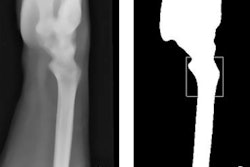

Craniocaudal view of a mammogram in left and right breast. The deep-learning-based CAD system identifies the area of the cancer (green box). All images courtesy of the Breast Research Group, INESC Porto in Portugal.

Mediolateral oblique view of a mammogram in left and right breast of the same woman. The deep-learning-based CAD system identifies the area of the cancer (green box).